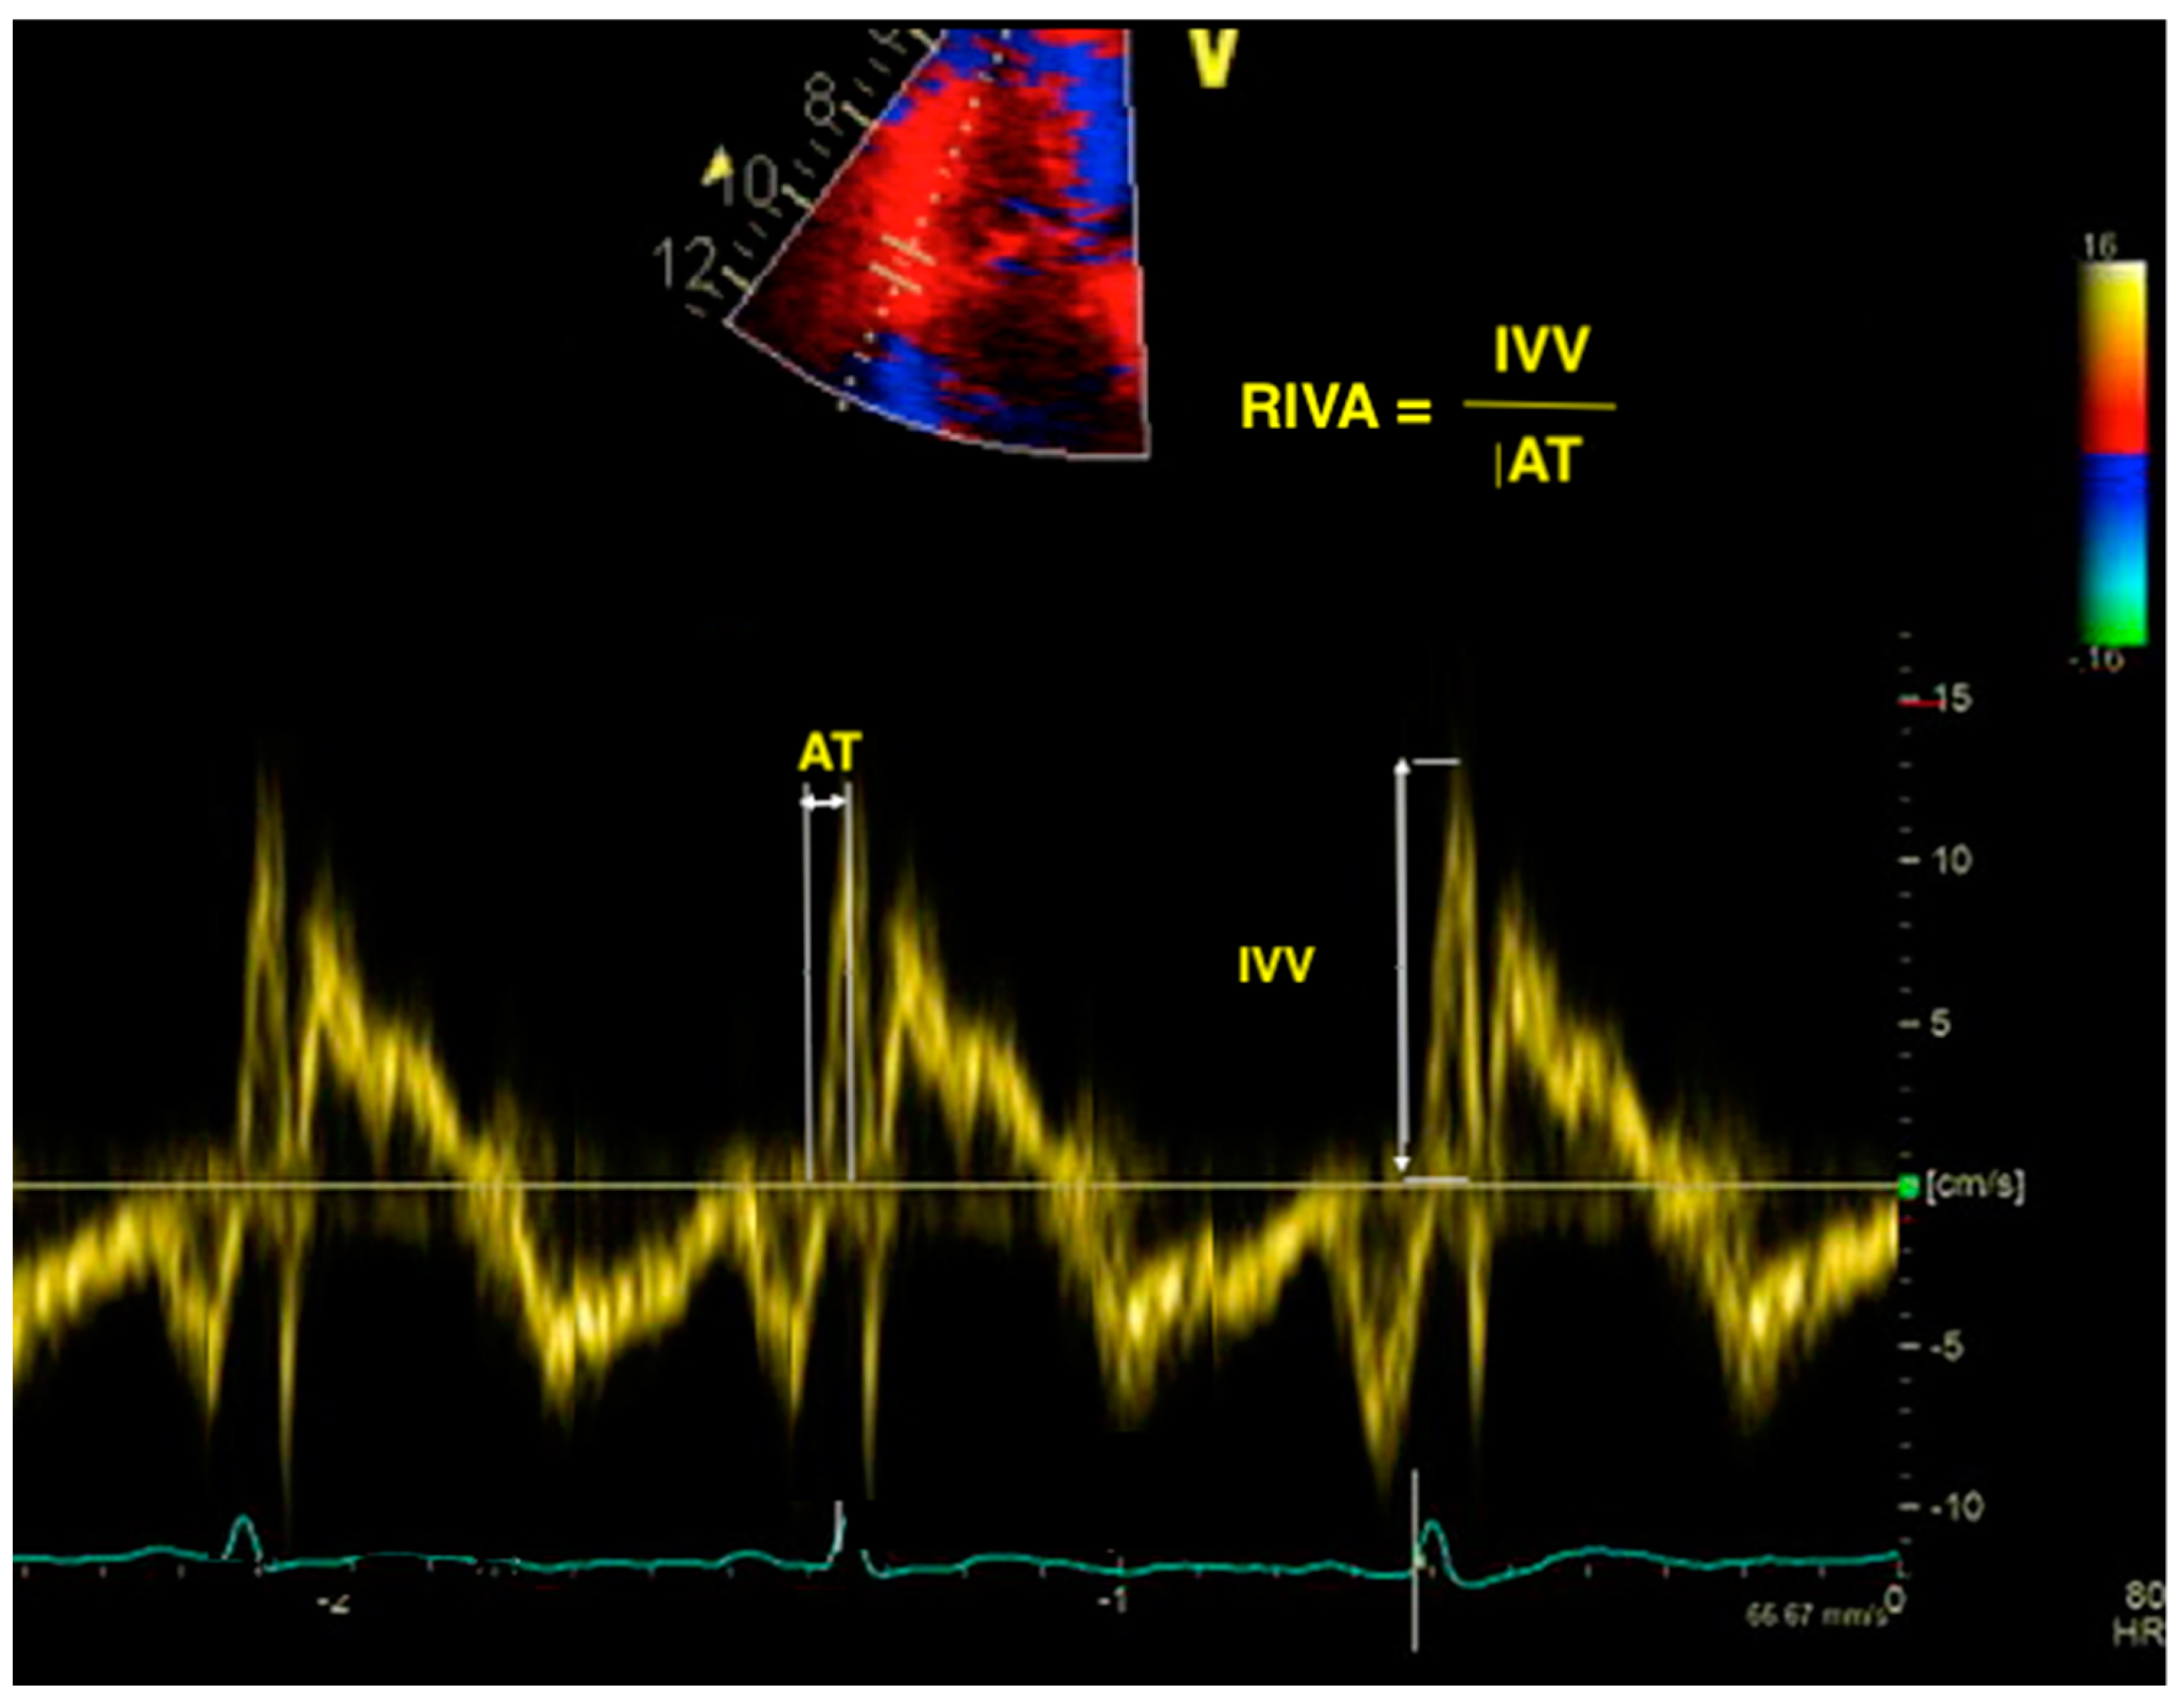

RIMP to assess RV Function What is RIMP? Rv Dysfunction In Echo rv dysfunction may be encountered in a wide variety of clinical scenarios. — rv function. — a comprehensive evaluation of the right ventricle (rv) by echocardiography is essential for the diagnosis and. The rate of pressure rise in the ventricles (dp/dt) is validated. Identifying the underlying aetiology is important in order to optimise rv. Normal function is. Rv Dysfunction In Echo.